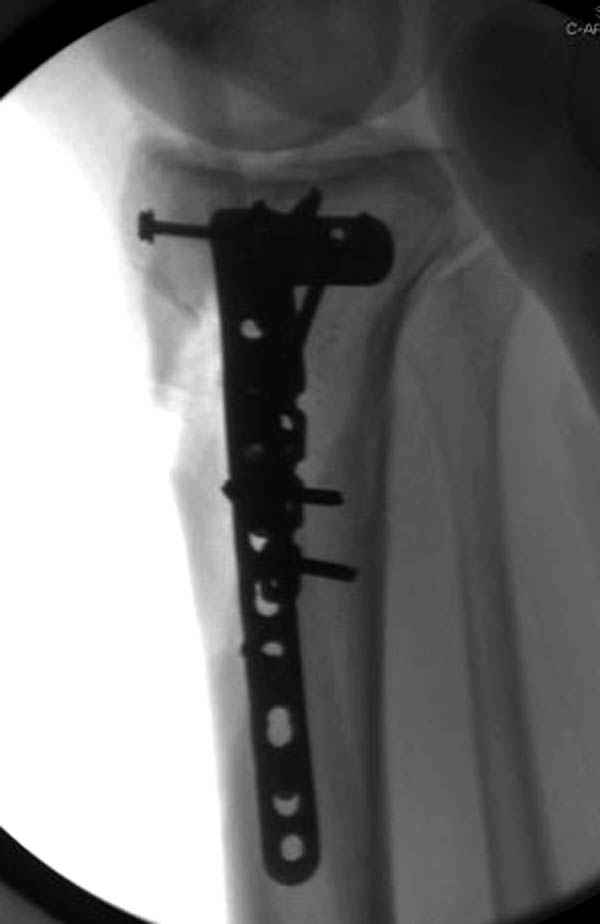

Такая ситуация характерна для многих, когда принимается ошибочное решение, т.е пытаются фиксировать одним имплантом переломы двух мыщелков. Латеральная пластина приемлема только для тех случаев, когда сохраняется интактным медиальный диафизарный кортекс и отсутствует фрагментация на верхушке медиального перелома.

При сложных переломах тибиал плато для своего рода Damage Control мы иногда применяем поэтапную тактику. Сперва оперируется одна сторона, а потом после рекондиции мягких тканей окончательный этап.

Если состояние мягких тканей позволяет, я бы предложил такой метод для вашего больного. Без предварительного планирования будет трудно, но шанс не надо упускать. Всего несколько дней после операции, и такая тактика лучше, чем недовольный молодой пациент.